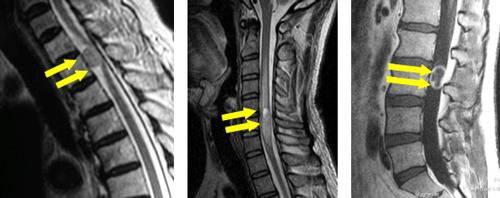

手術前のMRIでは、第6/7椎間の椎間板が脊柱管へ飛び出し、脊髄を強く圧迫しています。

手術により、飛び出した椎間板を前方から摘出し、人工スペーサーと金属製のプレートなどで上下の骨を固定しました。術後、神経症状は著明に改善し、MRIでも脊髄の圧迫が解除されています。

手術前のCTおよびMRIでは、椎体の後ろにある骨化した後縦靭帯が脊柱管内に大きく占拠し、脊髄を強く圧迫しています。

前方から椎体切除および骨化巣の浮上術を行い、代わりに金属製のケージを設置しました。非常に高度な狭窄であったため、後方からも除圧を追加し、頚椎のカーブを維持するためにスクリューとロッドによる固定を行いました。術後、神経症状は著明に改善しています。